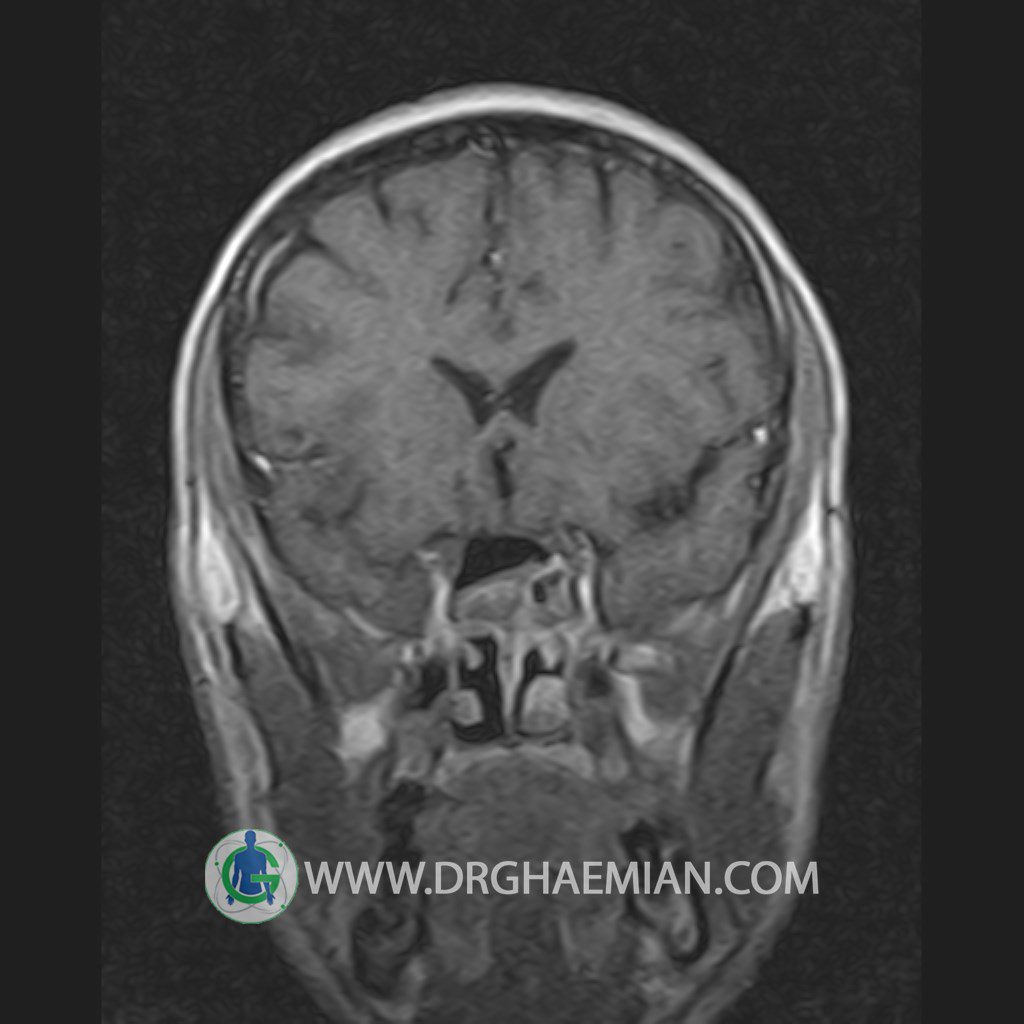

پزشکان اغلب از تصویربرداری ام آر آی برای تشخیص و درمان عارضه های پزشکی که فقط با استفاده از اشعه ایکس یا میدان مغناطیسی و امواج رادیویی قابل مشاهده است، استفاده می کنند. دستگاه ام آر آی تصاویر دقیق از ساختار های داخلی بدن ایجاد می کند. در این کیس یک میکروآدنوم در هیپوفیز بیمار مشاهده می شود.

HYPOPHYSIS MRI

(with and without contrast)

Technique: Axial , coronal T1 , Axial , coronal , sagittal T2 , Axial, coronal T1 post Gd & 64 dynamic thin coronal slices.

The infundibulum is centered and of normal size .

The optic chiasm and suprasellar spaces appear normal .

The cavernous sinus and imaged portions of the internal carotid artery and carotid siphon are unremarkable .

Evaluable portions of the neurocranium show no abnormalities .

The sphenoid sinus is clear and pneumatized .

Imaging of the hypothalamus after contrast medium administration was normal.

– Small hypoenhancing mass lesion ( 3 x 4 mm ) in posterior of pituitary stalk suggestive for micro adenoma

– Mucosal thickening in ethmoid & maxillary sinuses

is seen